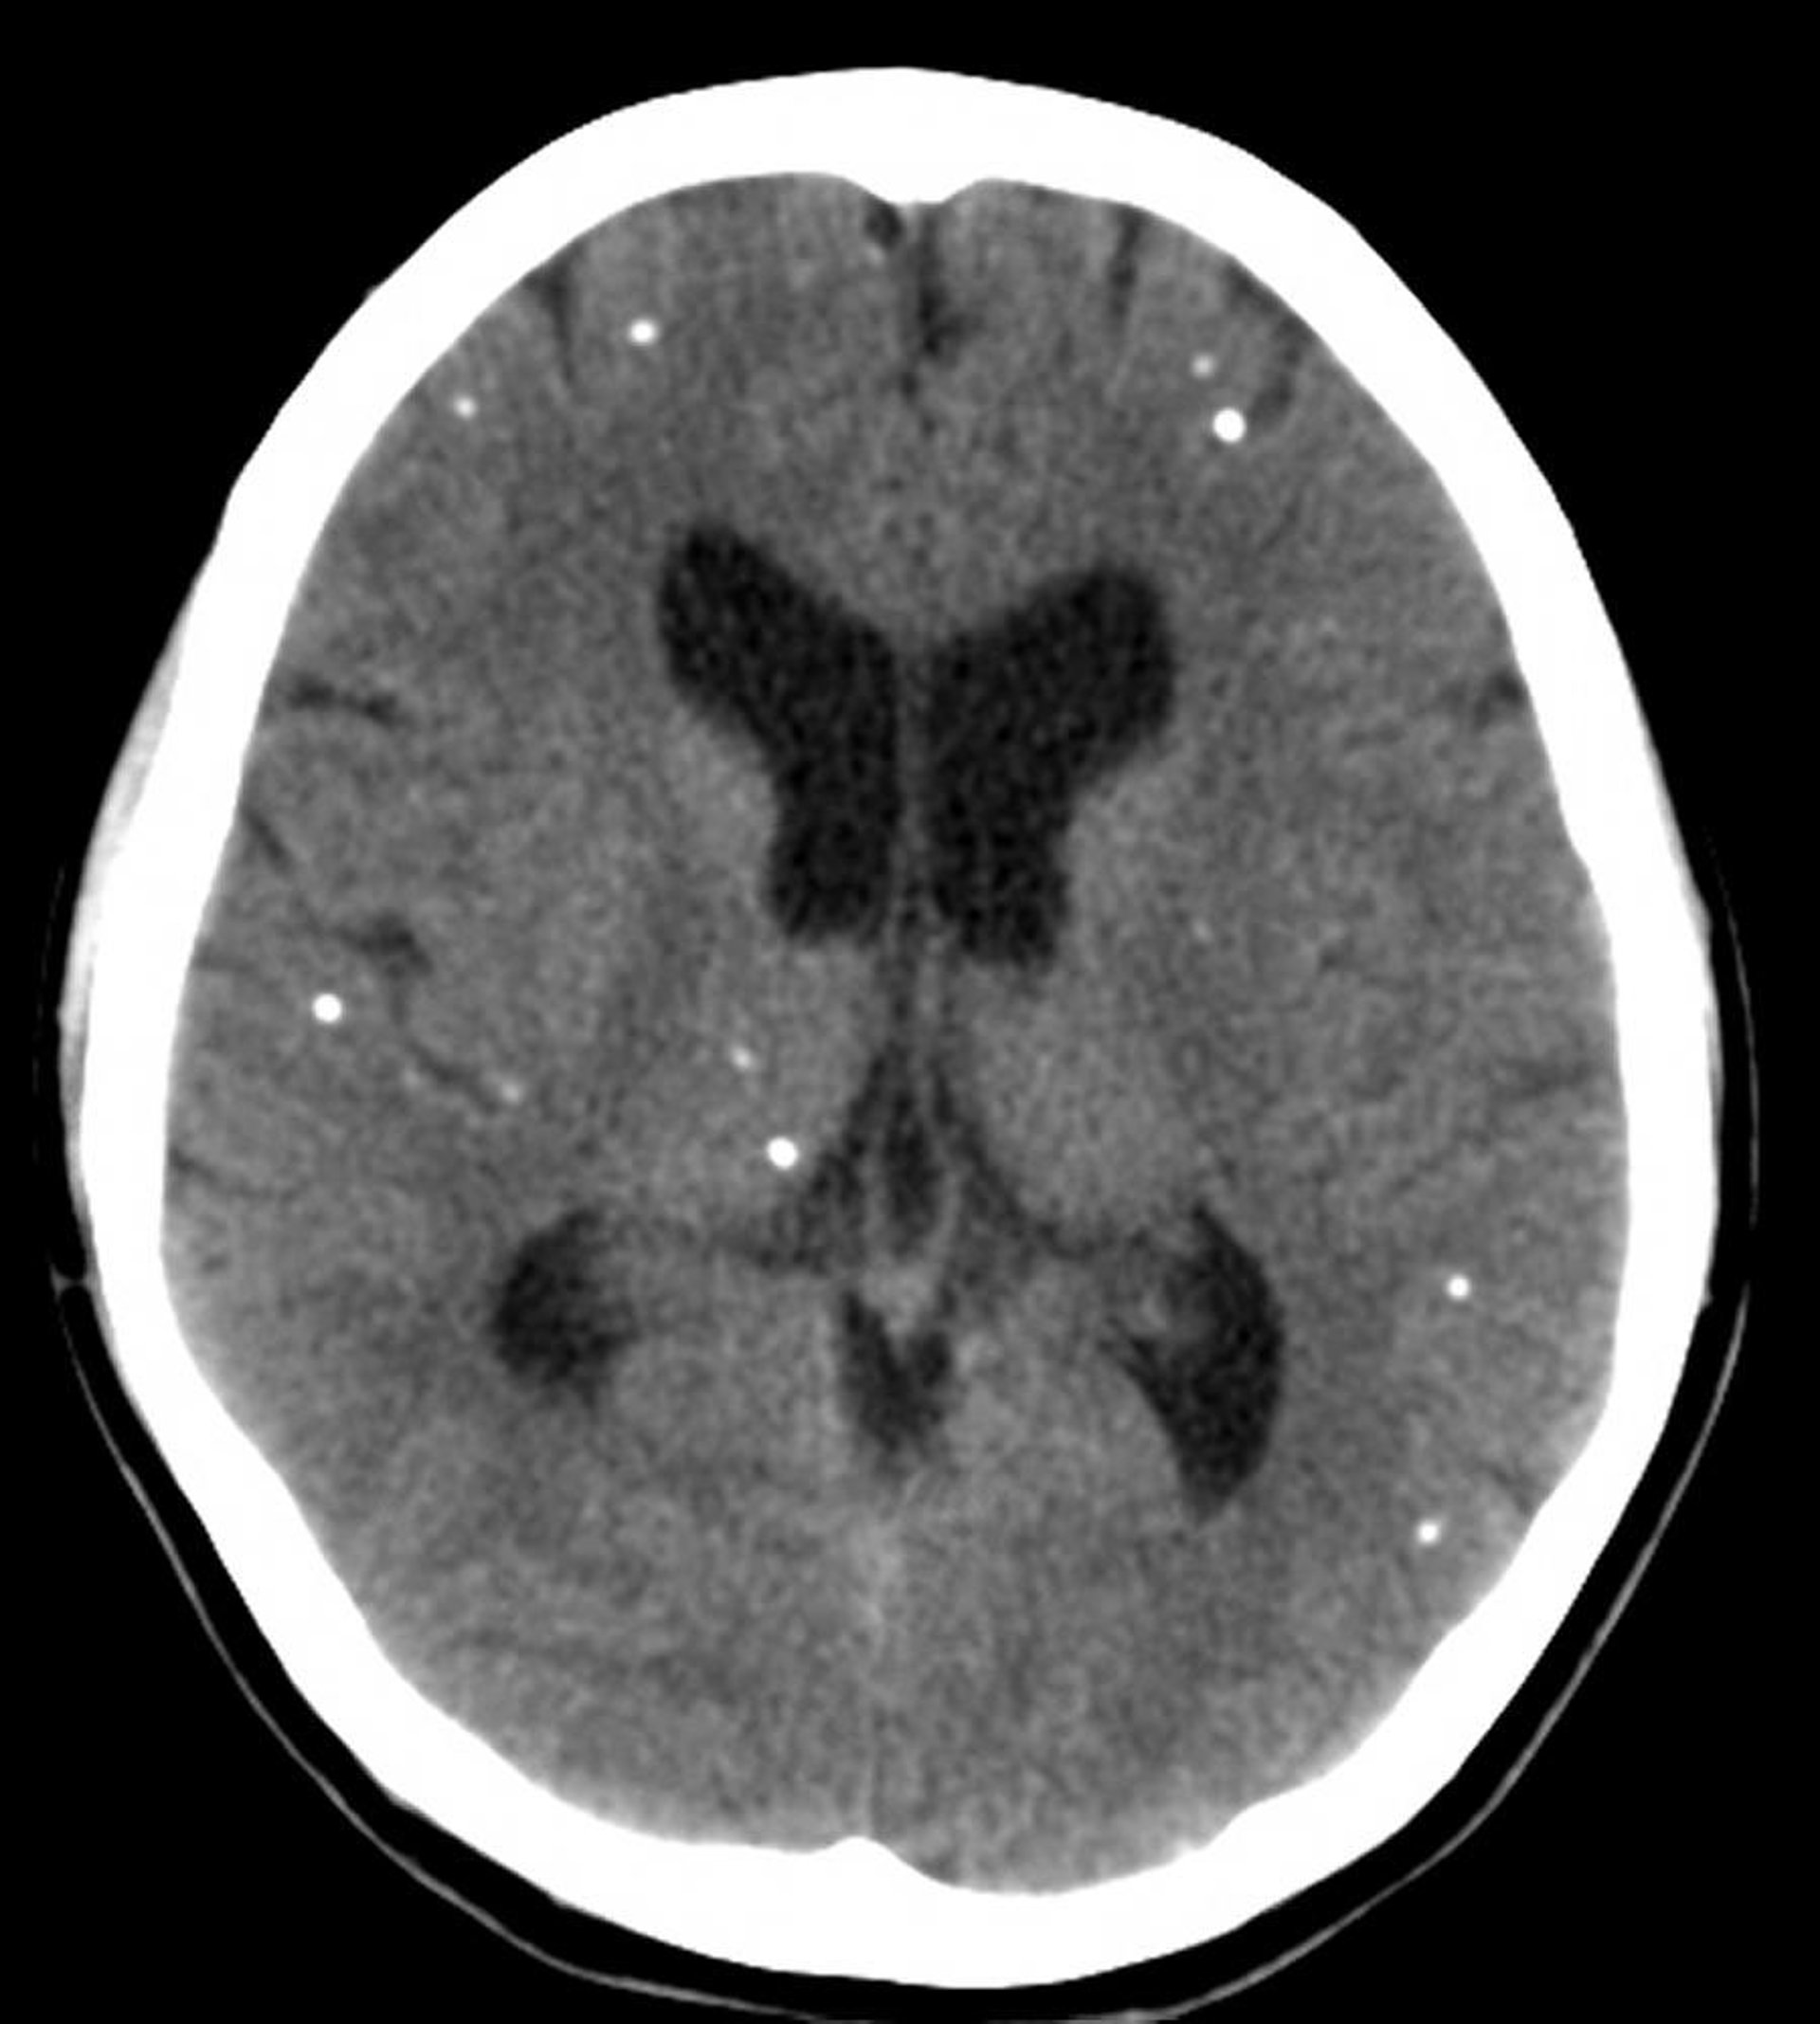

На этих снимках компьютерной томографии показаны множественные очаги кальцификации, представляющие кальцифицированные кисты у пациента с нейроцистицеркозом.

Courtesy of John E. Greenlee, MD.